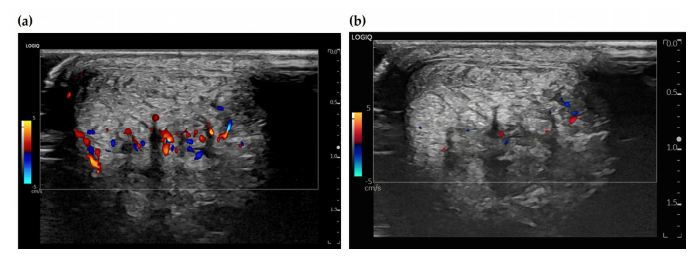

만성 건병증 부위에는 저산소 상태를 보상하기 위해 병적인 ‘신생 혈관’이 자라나는데, 이 신생 혈관을 따라 감각 신경 섬유도 함께 침투합니다. 이것이 지속적인 통증(신경성 염증)의 원인이 되죠

이럴 때, 초음파를 보면서 염증이 있는 부위에 고용량 약침을 주사해서 치료합니다.

PDRN 연아 약침, 태반 자하거 약침은 염증을 완화하고 조직 재생까지 돕습니다. > 4단계: 힘줄(tendon, 건)의 회복 > > 재생유도-Remodeling 마지막 단계는 아킬레스건이 뼈에 붙는 부위 즉, 건 부착부를 자극하여 건 자체의 퇴행을 회복시키는 단계입니다.

하지만 12회 치료 후 컬러 도플러 초음파상에서 병변 부위의 신생 혈관 신호가 현저히 감소한 것이확인되었습니다.**